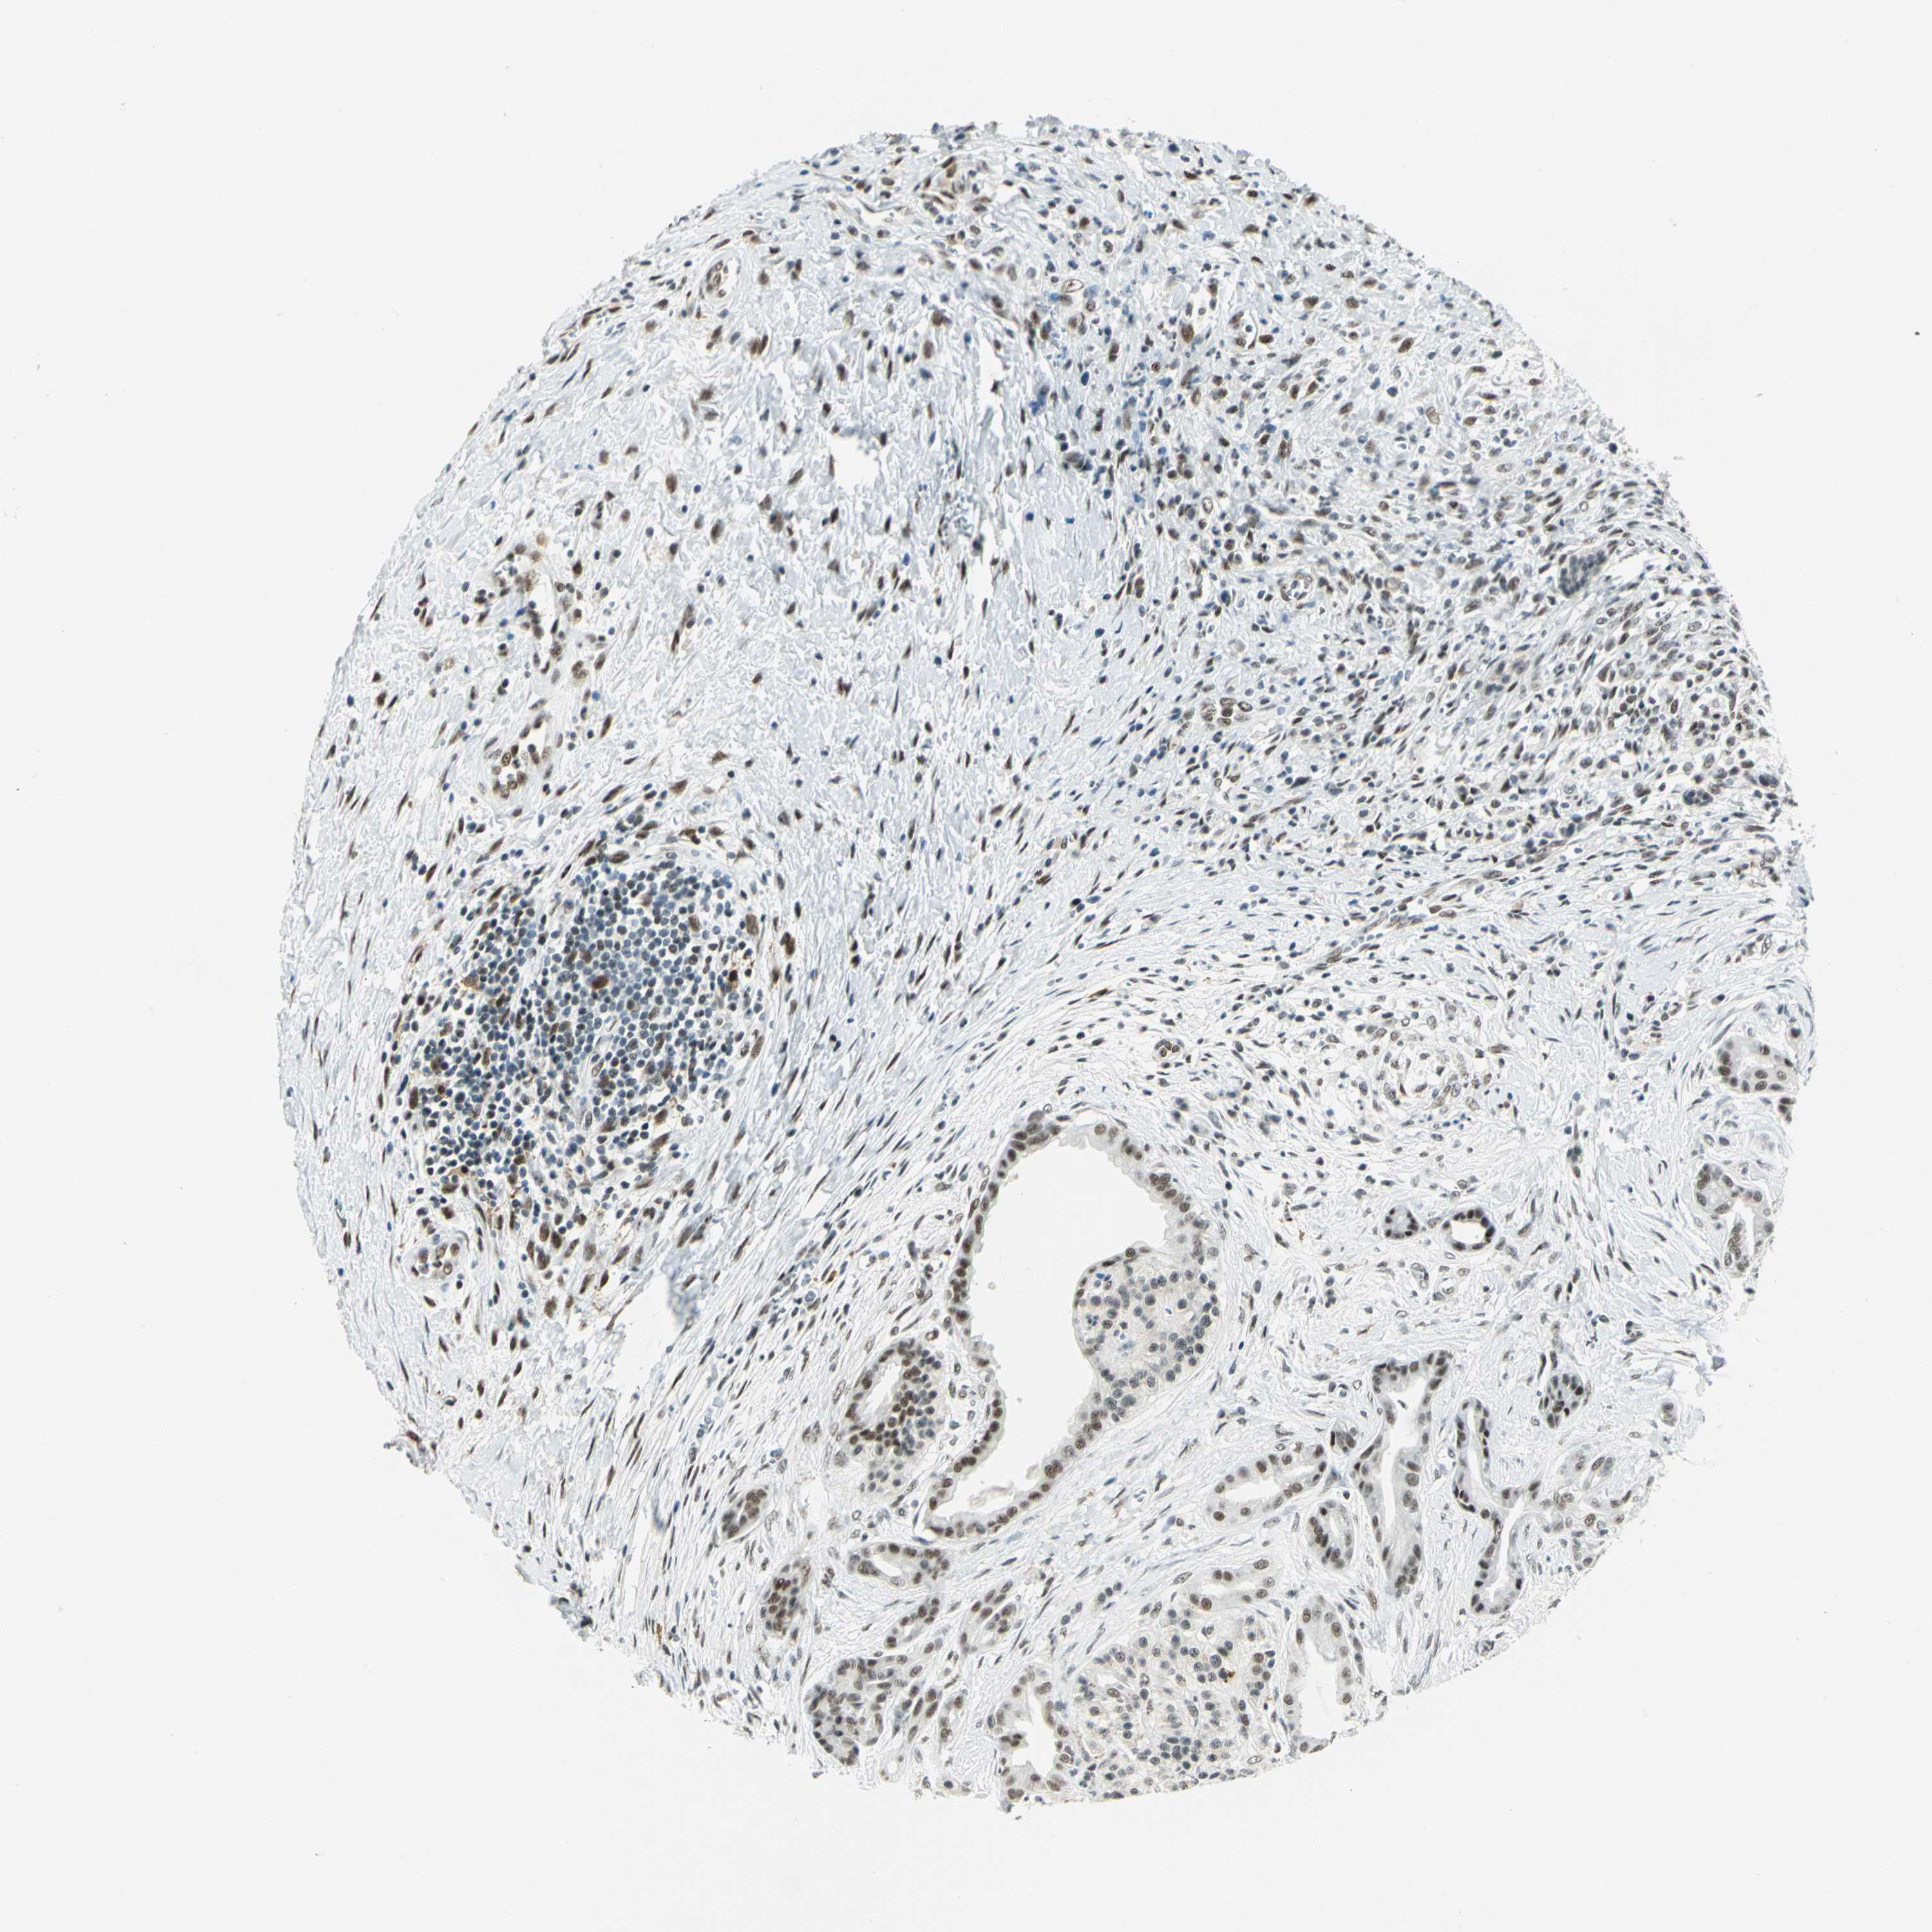

PANCREATIC CANCER - Protein expressioni

A mouse-over function shows sample information and annotation data. Click on an image to view it in a full screen mode. Samples can be filtered based on level of antibody staining by selecting one or several of the following categories: high, medium, low and not detected. The assay and annotation is described here.

Note that samples used for immunohistochemistry by the Human Protein Atlas do not correspond to samples in the TCGA dataset.

Antibody stainingi

Antibody staining in the annotated cell types in the current human tissue is reported as not detected, low, medium, or high, based on conventional immunohistochemistry profiling in selected tissues. This score is based on the combination of the staining intensity and fraction of stained cells.

Each image is clickable and will lead to virtual microscopy that enables deeper exploration of all samples and also displays staining intensity scores, fraction scores and subcellular localization as well as patient and tissue information for each sample.

Antibody HPA006081

Staining

High

Medium

Low

Not detected

Intensity

Strong

Moderate

Weak

Negative

Quantity

>75%

75%-25%

<25%

None

Location

Nuclear

Cytoplasmic/membranous

Cytoplasmic/membranous,nuclear

Adenocarcinoma, NOS

Adenocarcinoma, metastatic, NOS